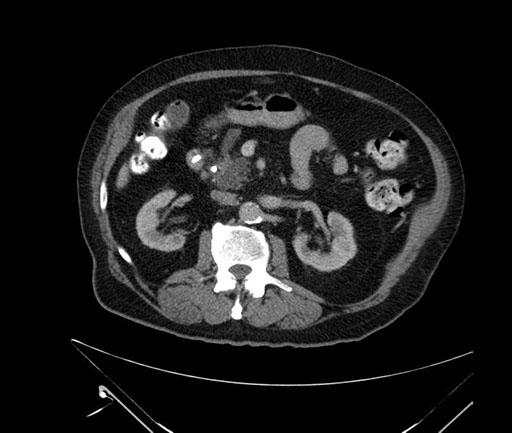

Whipple (pancreaticoduodenectomy) [case 7]

Imaging Analysis

Look through the patient's CT scan to identify any areas of concern for the necessary procedure.

Based on your CT findings, which issue(s) would give reason for "planned slowing down moment(s)" in this case?

Considering a standard Whipple procedure, what step(s) of the operation would you do differently in this case?